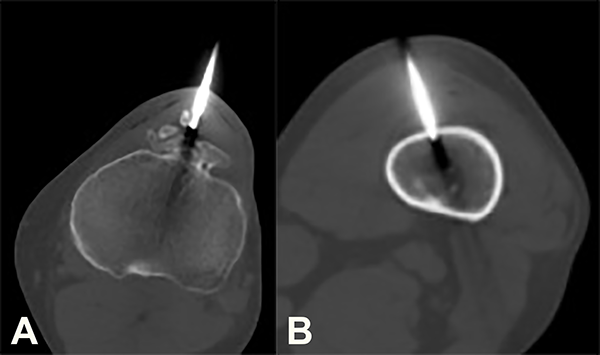

Se plantean como diagnósticos diferenciales: enfermedad de Trevor, una secuela de Osgood-Schlatter o un osteocondroma. Para establecer este diagnóstico se realizó una biopsia por punción de ambas lesiones guiada por TC (fig. 5).

El resultado de la anatomía patológica informó una proliferación osteocartilaginosa sin atipías la cual, asociada a las características radiológicas, corresponde a una displasia epifisaria hemimélica. En cuanto a la lesión del fémur, los hallazgos histológicos refieren a una displasia fibrosa.

Figura 5: Se observa el sitio de la biopsia guiada bajo TAC en un corte axial de la tibia (5a) y del fémur (5b).